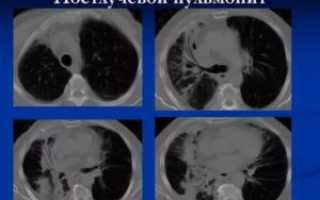

• Постлучевой пневмонит. Может развиваться при лучевой болезни или после курса облучения у больных с онкопатологией.

Пульмонит может развиться у людей, проходящих радиотерапию по поводу рака легких или молочной железы. Сам по себе он не является раковым заболеванием. Также патология иногда возникает после распространенной лучевой терапии, которая необходима при подготовке к пересадке костного мозга.

Воздействие вредного вещества не означает, что человек обязательно заболеет. Большую роль в развитии патологии играют генетические изменения. Например, риск заболеть выше, если в семье уже были случаи пульмонита. Также эта патология часто возникает при лучевой терапии легких по поводу рака (постлучевой пневмонит).